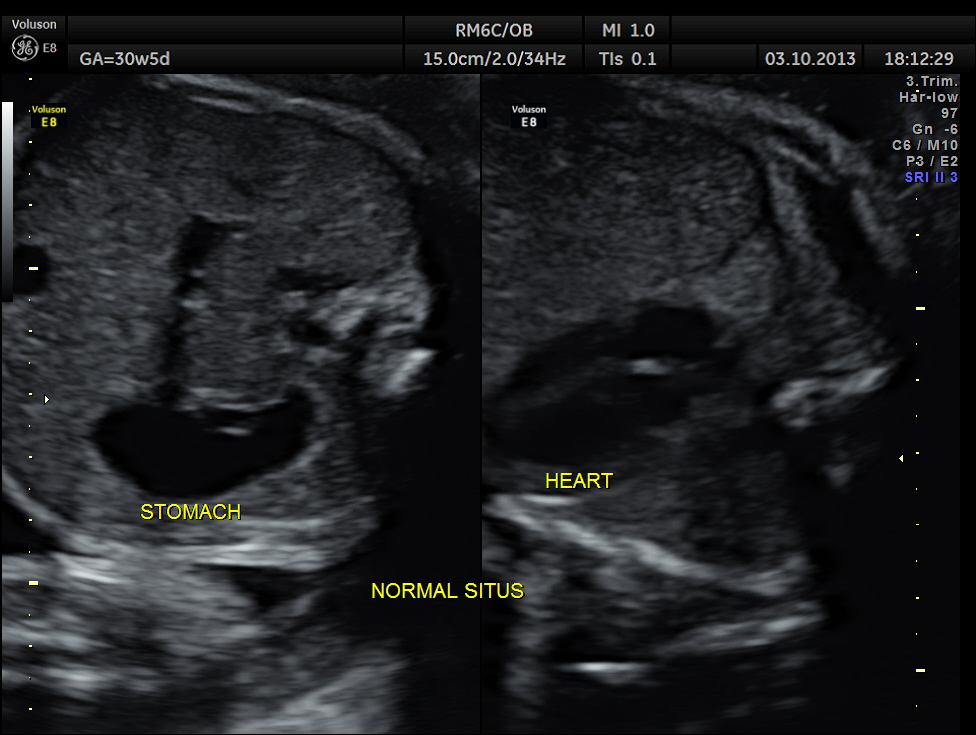

The following pictures belong to two scans done at 31 weeks of gestation.

The rest of the scan appeared normal.